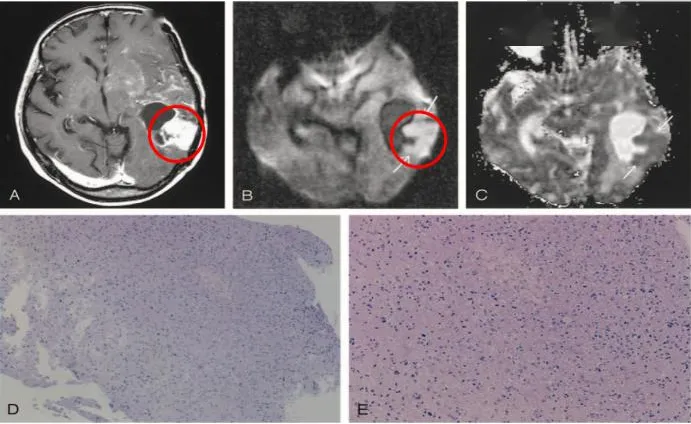

一例间变型星形细胞瘤放化疗后dwi影像及病理改变

从定义上看,3级肿瘤是恶性的,因为它们积极地繁殖侵袭周围组织的异常细胞。它们可以3级或4级的形式存在,具有循环往复的倾向。在手术后,3级和4级肿瘤往往需要外的治疗,特别是放射疗法和化学疗法的介入。3级肿瘤的一个代表是间变型星形细胞瘤。

胶质母细胞瘤组织学形态

4级肿瘤是恶性程度高且具侵袭性的脑肿瘤。在显微镜观察下,它们的细胞极其异常。它们会征集新的血管以维持自身快速的生长。胶质母细胞瘤是常见的4级脑肿瘤。